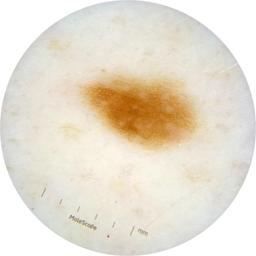

ISIC_9751750

2009 x 2009

acquisition_day 410

age_approx 50

anatom_site_1 Trunk

anatom_site_2 Posterior trunk

anatom_site_general posterior torso

diagnosis_1 Benign

diagnosis_confirm_type single image expert consensus

image_type dermoscopic